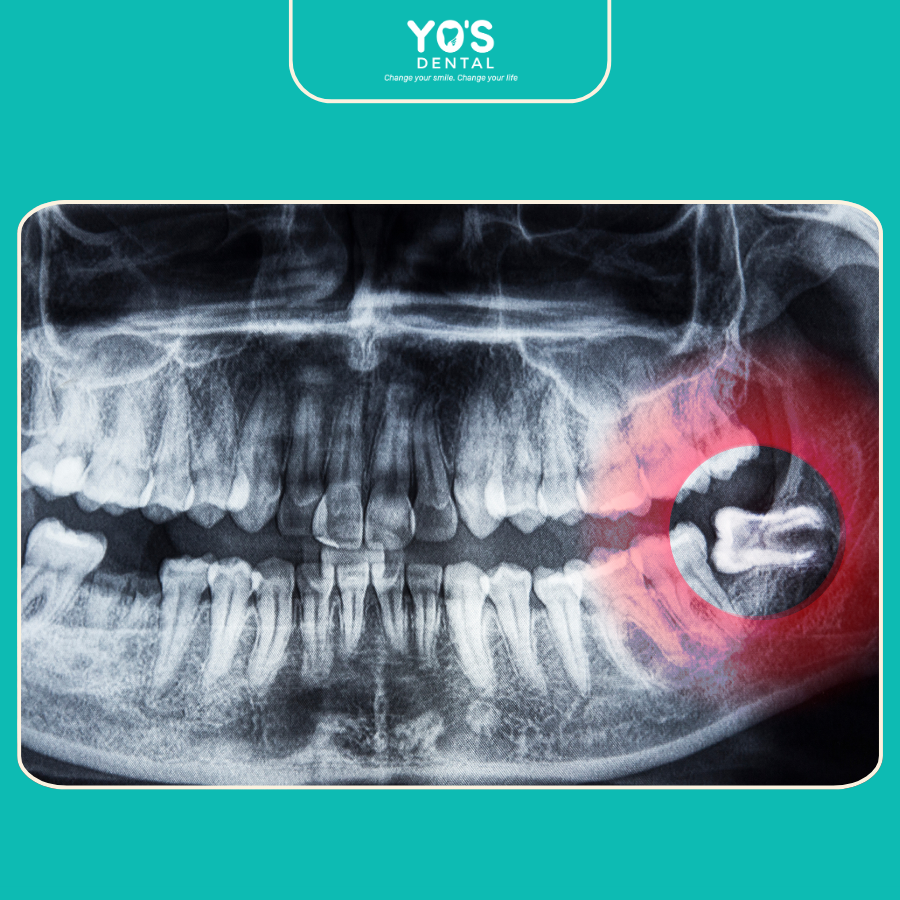

Răng Khôn Mọc Lệch Hoặc Ngầm

Răng khôn mọc lệch là tình trạng khá phổ biến, khi chiếc răng không mọc thẳng mà đâm ngang vào các răng bên cạnh. Điều này có thể gây ra áp lực lên các răng khác, làm chúng bị chen chúc hoặc lệch vị trí.

Trong một số trường hợp, răng khôn thậm chí không thể trồi lên khỏi lợi, gây ra hiện tượng răng khôn mọc ngầm và dẫn đến các biến chứng nghiêm trọng.